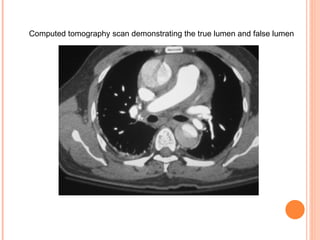

Computed tomography scan demonstrating the true lumen and false lumen

Computed tomography scandemonstrating the true lumen and false lumen